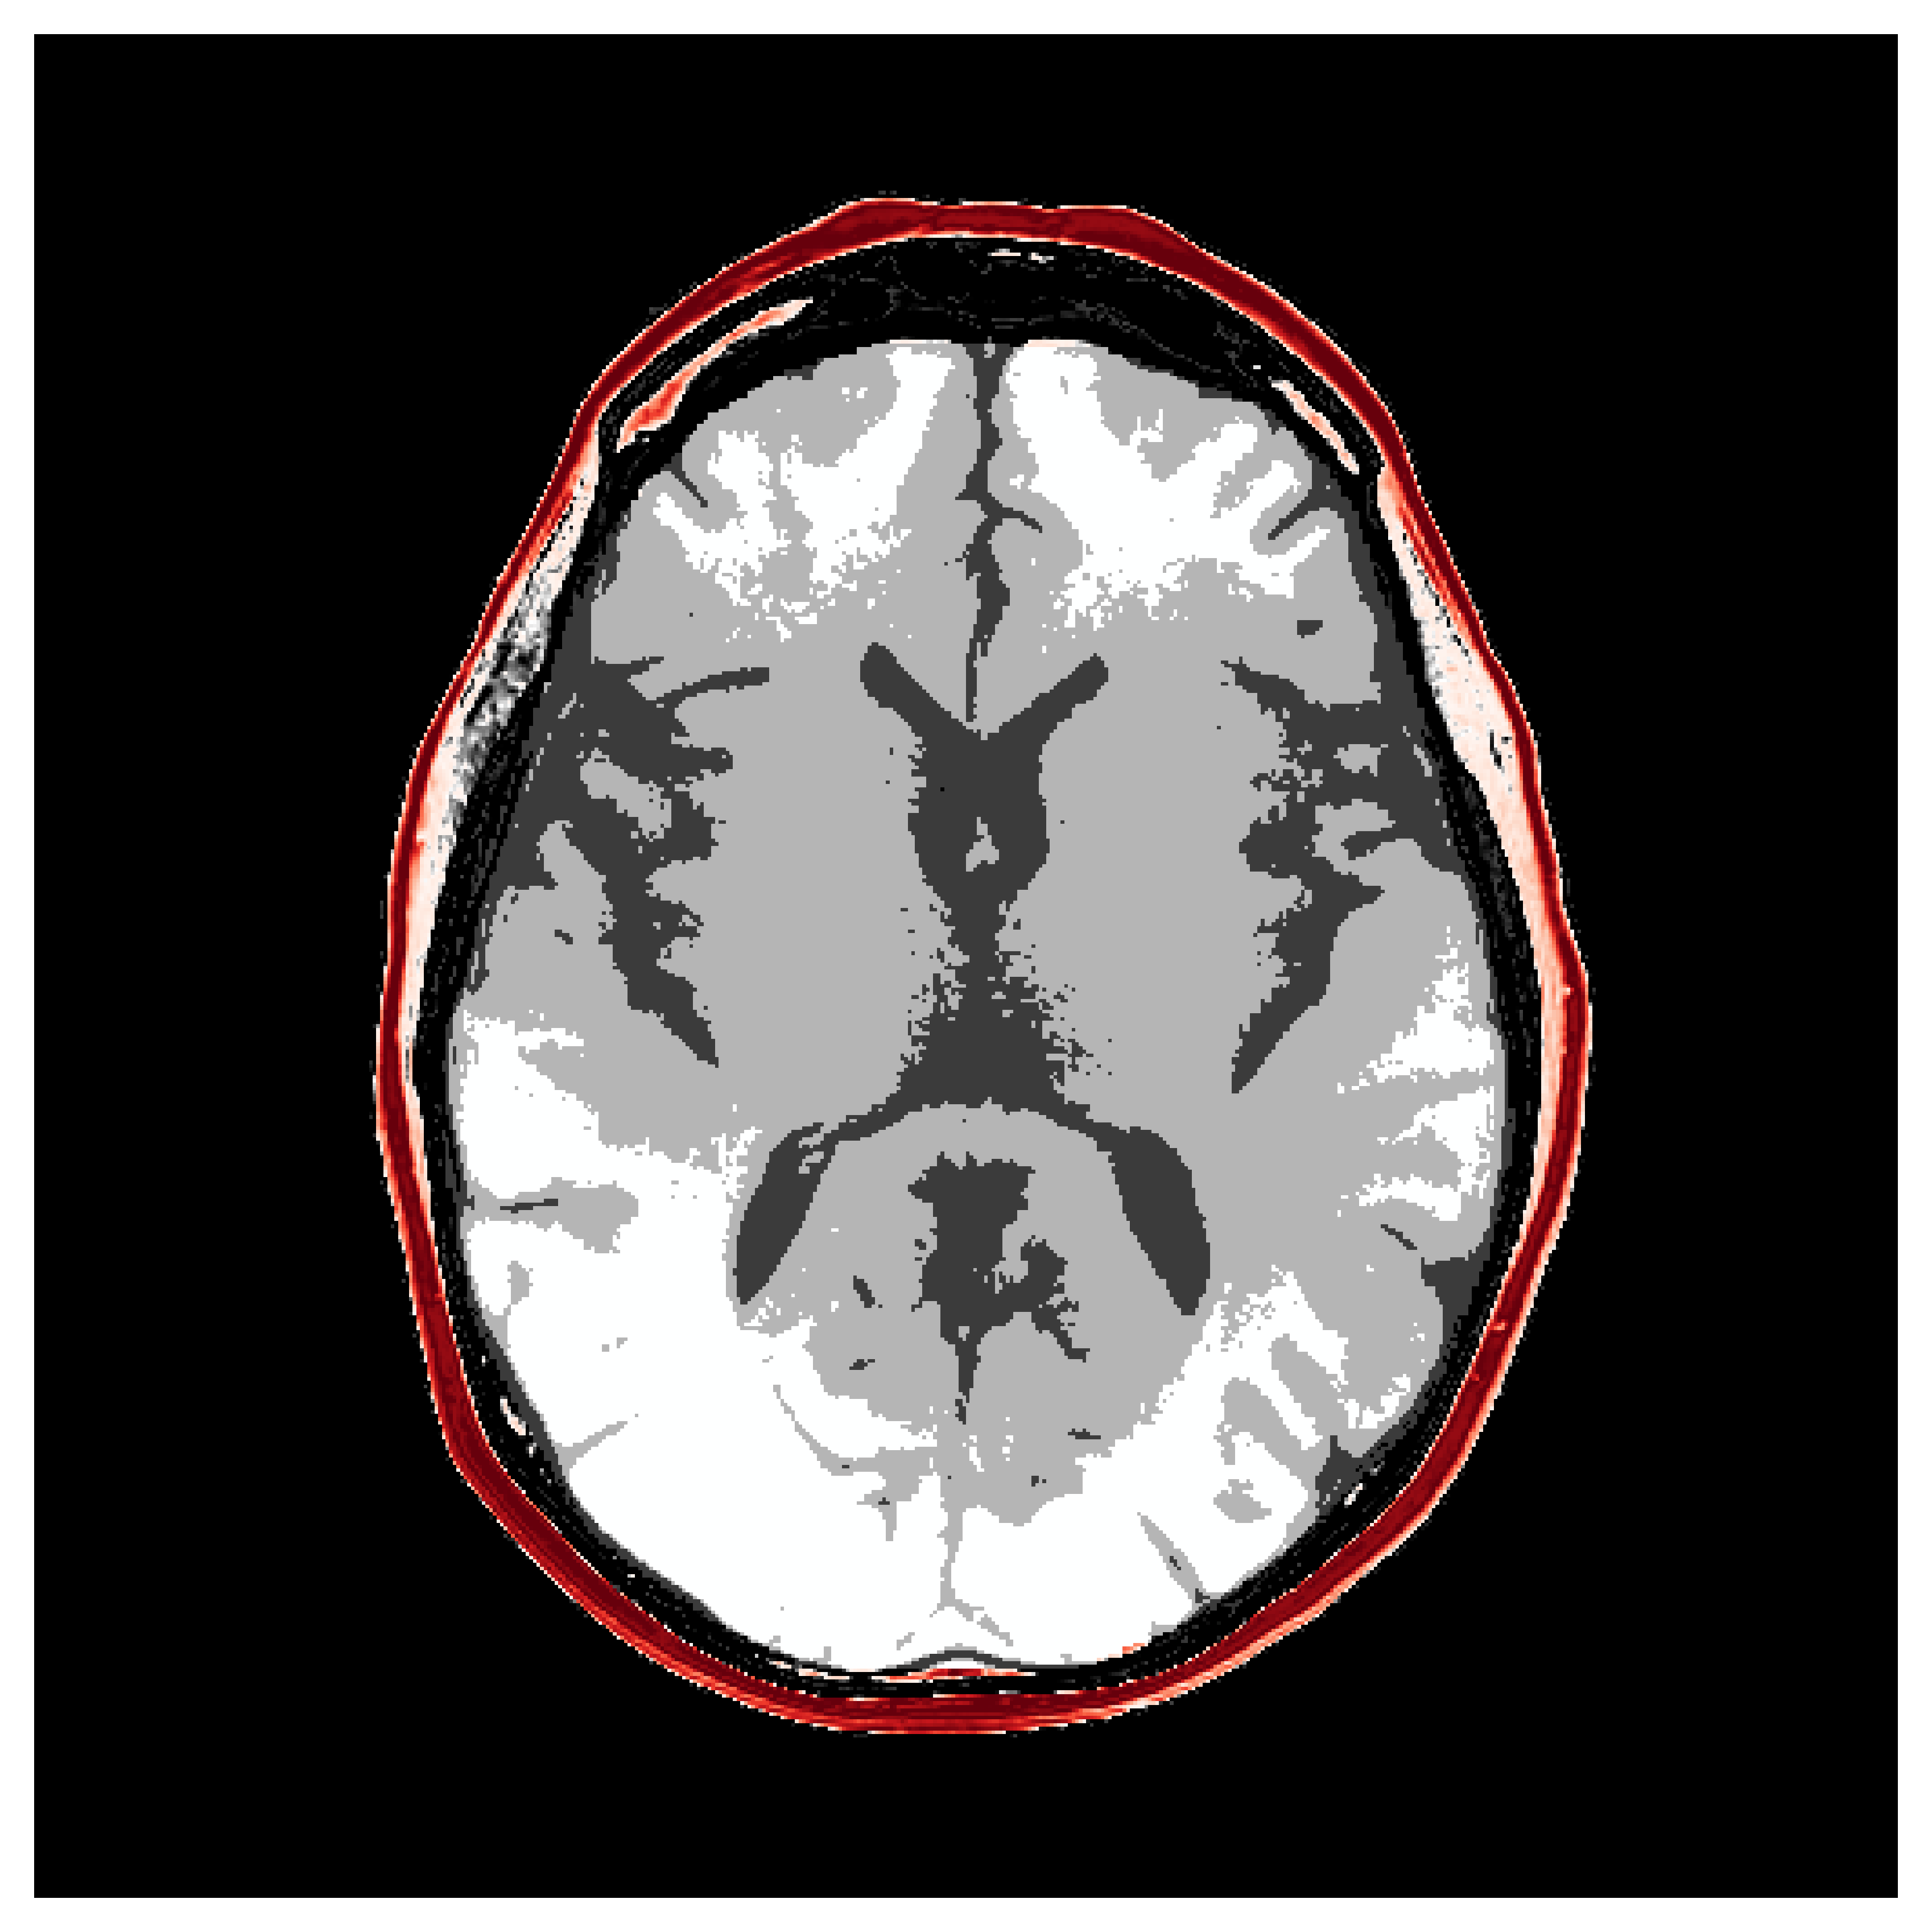

4.2.1 Brain prior samples:

The first step of implementing ASPIRE concerns obtaining samples from a realistic prior for the target parameter vector , in this case, gridded velocity parameters of human brains and skulls. The parameters collected in the MIDA dataset [56] correspond to a single 3D volume for the acoustic velocity collected from a single subject and will unfortunately not be appropriate to train a neural model that will generalize to other human patients. As far as we know, there is no dataset that includes acoustic velocity collected from many patients, so we made our own dataset based off the multi-subject FASTMRI dataset [57]. This custom dataset, detailed in Section \thechapter.A, comprises N=1000 diverse acoustic velocity parameters collected from different human patients, . This size of datasets facilitates generalization of the amortized posterior sampler across different datasets collected from unseen patients. The dataset is accessible via the repo ASPIRE.jl.

Appendix \thechapter.A FASTMRI acoustic dataset creation

Based off of the MRI dataset [57], we manually assigned acoustic values to MRI intensities by following the table of acoustic brain tissue properties in the supplemental section of [47]. Although MRI intensities are not necessarily related to acoustic tissue properties, we found that we could produce reasonably realistic acoustic parameters as compared to the acoustic parameters from the MIDA volume. In Figure 19, we show some example training acoustic parameters. We also plot the average and standard variation between all 1000 training samples in Figure 20. From these plots, we note that there are few similarities between training examples apart from the biologically consistent human brain structures.